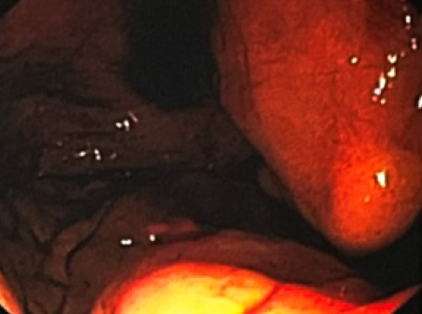

入院后查胃镜(图1):胃底及胃体见多条静脉曲张团,见血凝块及陈旧性出血,予三明治夹心法注射黏合剂4ml,拔针后喷血,再注射2ml出血停止。

图1 胃镜下检查